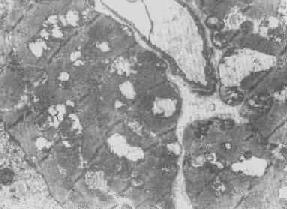

图1-10肾小管上皮细胞线粒体部分空泡变

图1-11 线粒体肿胀(基质型)空泡变(心肌缺氧) 3.结构的改变 线粒体嵴是能量代谢的明显指征,但嵴的增多未必均伴有呼吸链酶的增加。嵴的膜和酶平行增多反映细胞的功能负荷加重,为一种适应状态的表现;反之,如嵴的膜和酶的增多不相平行,则是胞浆适应功能障碍的表现,此时细胞功能并不升高。 在急性细胞损伤时(大多为中毒或缺氧),线粒体的嵴被破坏;慢性亚致死性细胞损伤或营养缺乏时,线粒体的蛋白合成受障,以致线粒体几乎不再能形成新的嵴。 根据细胞损伤的种类和性质,可在线粒体基质或嵴内形成病理性包含物。这些包含物有的呈晶形或副晶形(可能由蛋白构成),如在线粒体性肌病或进行性肌营养不良时所见(图1-12);有的呈无定形的电子致

四、线粒体线粒体(mitochondrion)是细胞内主要的能量形成所在,故不论在生理上或病理上都具有十分重要的意义。 线粒体为线状、长杆状、卵圆形或圆形小体,外被双层界膜。外界膜平滑,内界膜则折成长短不等的嵴并附有基粒。内外界膜之间为线粒体的外室,与嵴内隙相连,内界膜内侧为内室(基质室)(图1-8)。在合成甾类激素的内分泌细胞(如肾上腺皮质细胞、卵甾滤泡细胞、睾丸的Leydig细胞等),线粒体嵴呈小管状。内外界膜的通透性不同,外界膜的通透性高,可容许多种物质通过,而内界膜则构成明显的通透屏障,使一些物质如蔗糖和NADH全然不能通过,而其他物质如Na+ 和Ca 2+等也只有借助于主动运输才能通过。线粒体的基质含有电子致密的无结构颗粒(基质颗粒),与二价阳离子如Ca2+及Mg2+具有高度亲和力。基质中进行着β氧化、氧化脱羧、枸橼酸循环以及尿素循环等过程。在线粒体的外界膜内含有单胺氧化酶以及糖和脂质代谢的各种转移酶;在内界膜上则为呼吸链和氧化磷酸化的酶类。 线粒体是对各种损伤最为敏感的细胞器之一。在细胞损伤时最常见的病理改变可概括为线粒体数量、大小和结构的改变: 1.数量的改变 线粒体的平均寿命约为10天。衰亡的线粒体可通过保留的线粒体直接分裂为二予以补充。在病理状态下,线粒体的增生实际上是对慢性非特异性细胞损伤的适应性反应或细胞功能升高的表现。例如心瓣膜病时的心肌线粒体、周围血液循环障碍伴间歇性跛行时的骨骼肌线粒体的呈增生现象。 线粒体数量减少则见于急性细胞损伤时线粒体崩解或自溶的情况下,持续约15分钟。慢性损伤时由于线粒体逐渐增生,故一般不见线粒体减少(甚至反而增多)。此外,线粒体的减少也是细胞未成熟和(或)去分化的表现。 2.大小改变 细胞损伤时最常见的改变为线粒体肿大。根据线粒体的受累部位可分为基质型肿胀和嵴型肿胀二种类型,而以前者为常见。基质型肿胀时线粒体变大变圆,基质变浅、嵴变短变少甚至消失(图1-9)。在极度肿胀时,线粒体可转化为小空泡状结构(图1-10,图1-11)。此型肿胀为细胞水肿的部分改变。光学显微镜下所谓的浊肿细胞中所见的细颗粒即肿大的线粒体。嵴型肿较少见,此时的肿胀局限于嵴内隙,使扁平的嵴变成烧瓶状乃至空泡状,而基质则更显得致密。嵴型肿胀一般为可复性,但当膜的损伤加重时,可经过混合型而过渡为基质型。 线粒体为对损伤极为敏感的细胞器,其肿胀可由多种损伤因子引起,其中最常见的为缺氧;此外,微生物毒素、各种毒物、射线以及渗透压改变等亦可引起。但轻度肿大有时可能为其功能升高的表现,较明显的肿胀则恒为细胞受损的表现。但只要损伤不过重、损伤因子的作用不过长,肿胀仍可恢复。 线粒体的增大有时是器官功能负荷增加引起的适应性肥大,此时线粒体的数量也常增多,例如见于器官肥大时。反之,器官萎缩时,线粒体则缩小、变少。